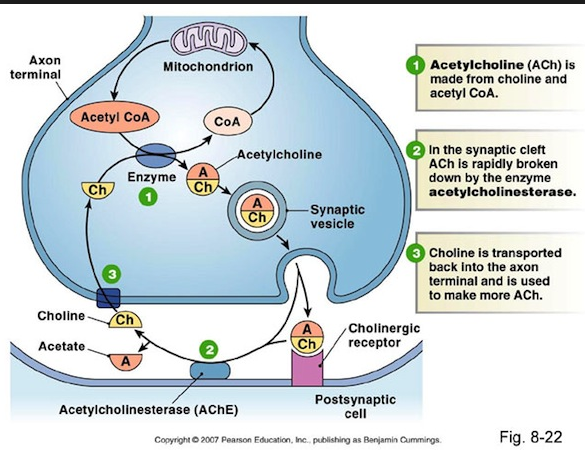

and the LINK to the bio-molecular communications molecule ……ace –> acetylcholine

Acetylcholine – Wikipedia, the free encyclopedia

https://en.wikipedia.org/wiki/Acetylcholine

Wikipedia

Acetylcholine is an organic chemical that functions in the brain and body of many types of animals, including humans, as a neurotransmitter—a chemical …

History · Function · Synthesis and degradation · Receptors

Acetylcholine Neurotransmission (Section 1, Chapter 11 …

neuroscience.uth.tmc.edu › Table of Contents

11.1 Introduction. Acetylcholine, the first neurotransmitter discovered, was originally described as “vagus stuff” by Otto Loewi because of its ability to mimic the …

Acetylcholine – Neuroscience – NCBI Bookshelf

www.ncbi.nlm.nih.gov › … › Bookshelf

National Center for Biotechnology Information

by D Purves – 2001

Acetylcholine is the neurotransmitter at neuromuscular junctions, at synapses in the ganglia of the visceral motor system, and at a variety of sites within the …

Choline transporter —> newspaper messages via –> Cho + line –> Mr. Cho an English major and Virginia tech and his line(s) …. choline messages

Acetylcholine – Wikipedia, the free encyclopedia

https://en.wikipedia.org/wiki/Acetylcholine

Wikipedia

Acetylcholine is an organic chemical that functions in the brain and body of many types of ….. The enzyme acetylcholinesterase converts acetylcholine into the inactive metabolites choline andacetate. This enzyme is abundant in the synaptic …

acetylcholinesterase converts acetylcholine into the inactive metabolites choline and acetate.

the inactive metabolites choline and acetate.

the inactive metabolites choline and acetate.

the inactive metabolites ……………….acetate.

the inactive metabolites ……………….ace …. tate.